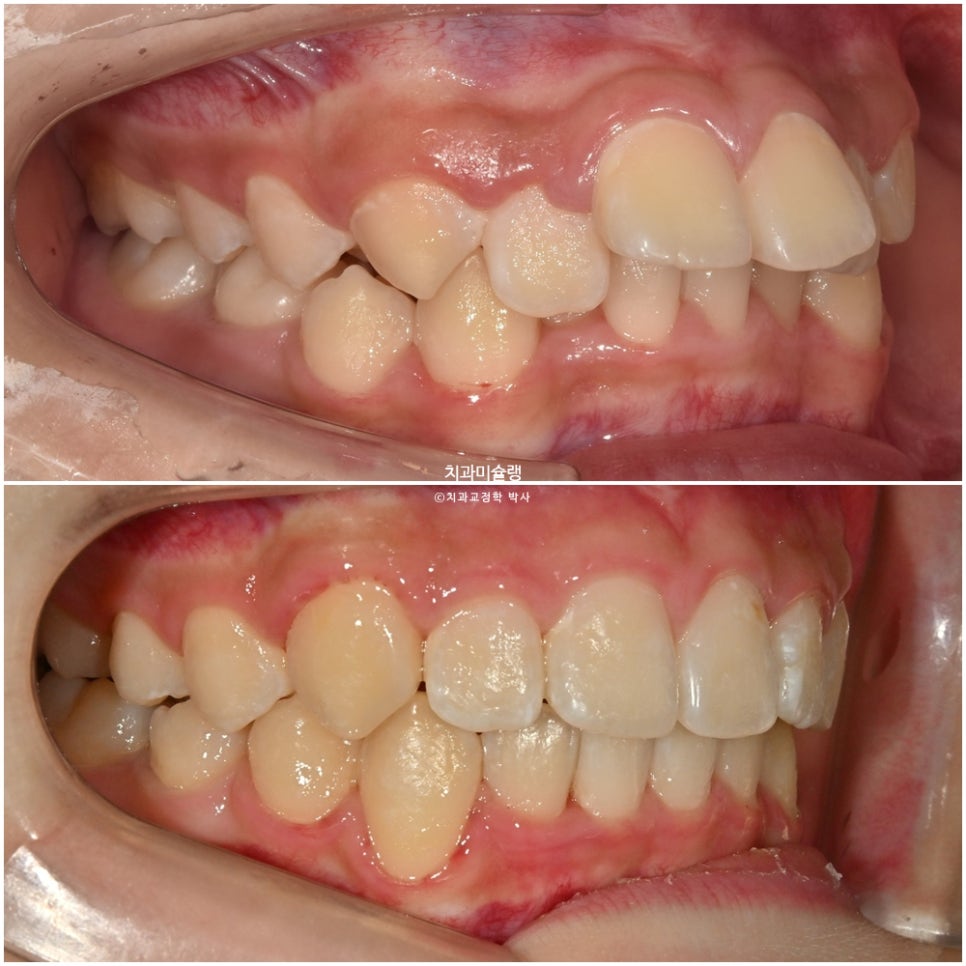

좌우 교합관계가 모두 2급이며 특히 좌측이 더 심합니다.

어금니 교합관계는 고무줄을 계속 걸었던 우측은 1급을 달성, 고무줄을 못걸었던 좌측은 여전히 2급 입니다.

배열은 좋습니다. 일년사이 마지막 남아있던 유치가 빠지고 영구치가 올라왔습니다.

어금니 교합관계는 양쪽다 1급을 달성.

2급 교합관계가 1급 교합관계로 개선되었습니다.